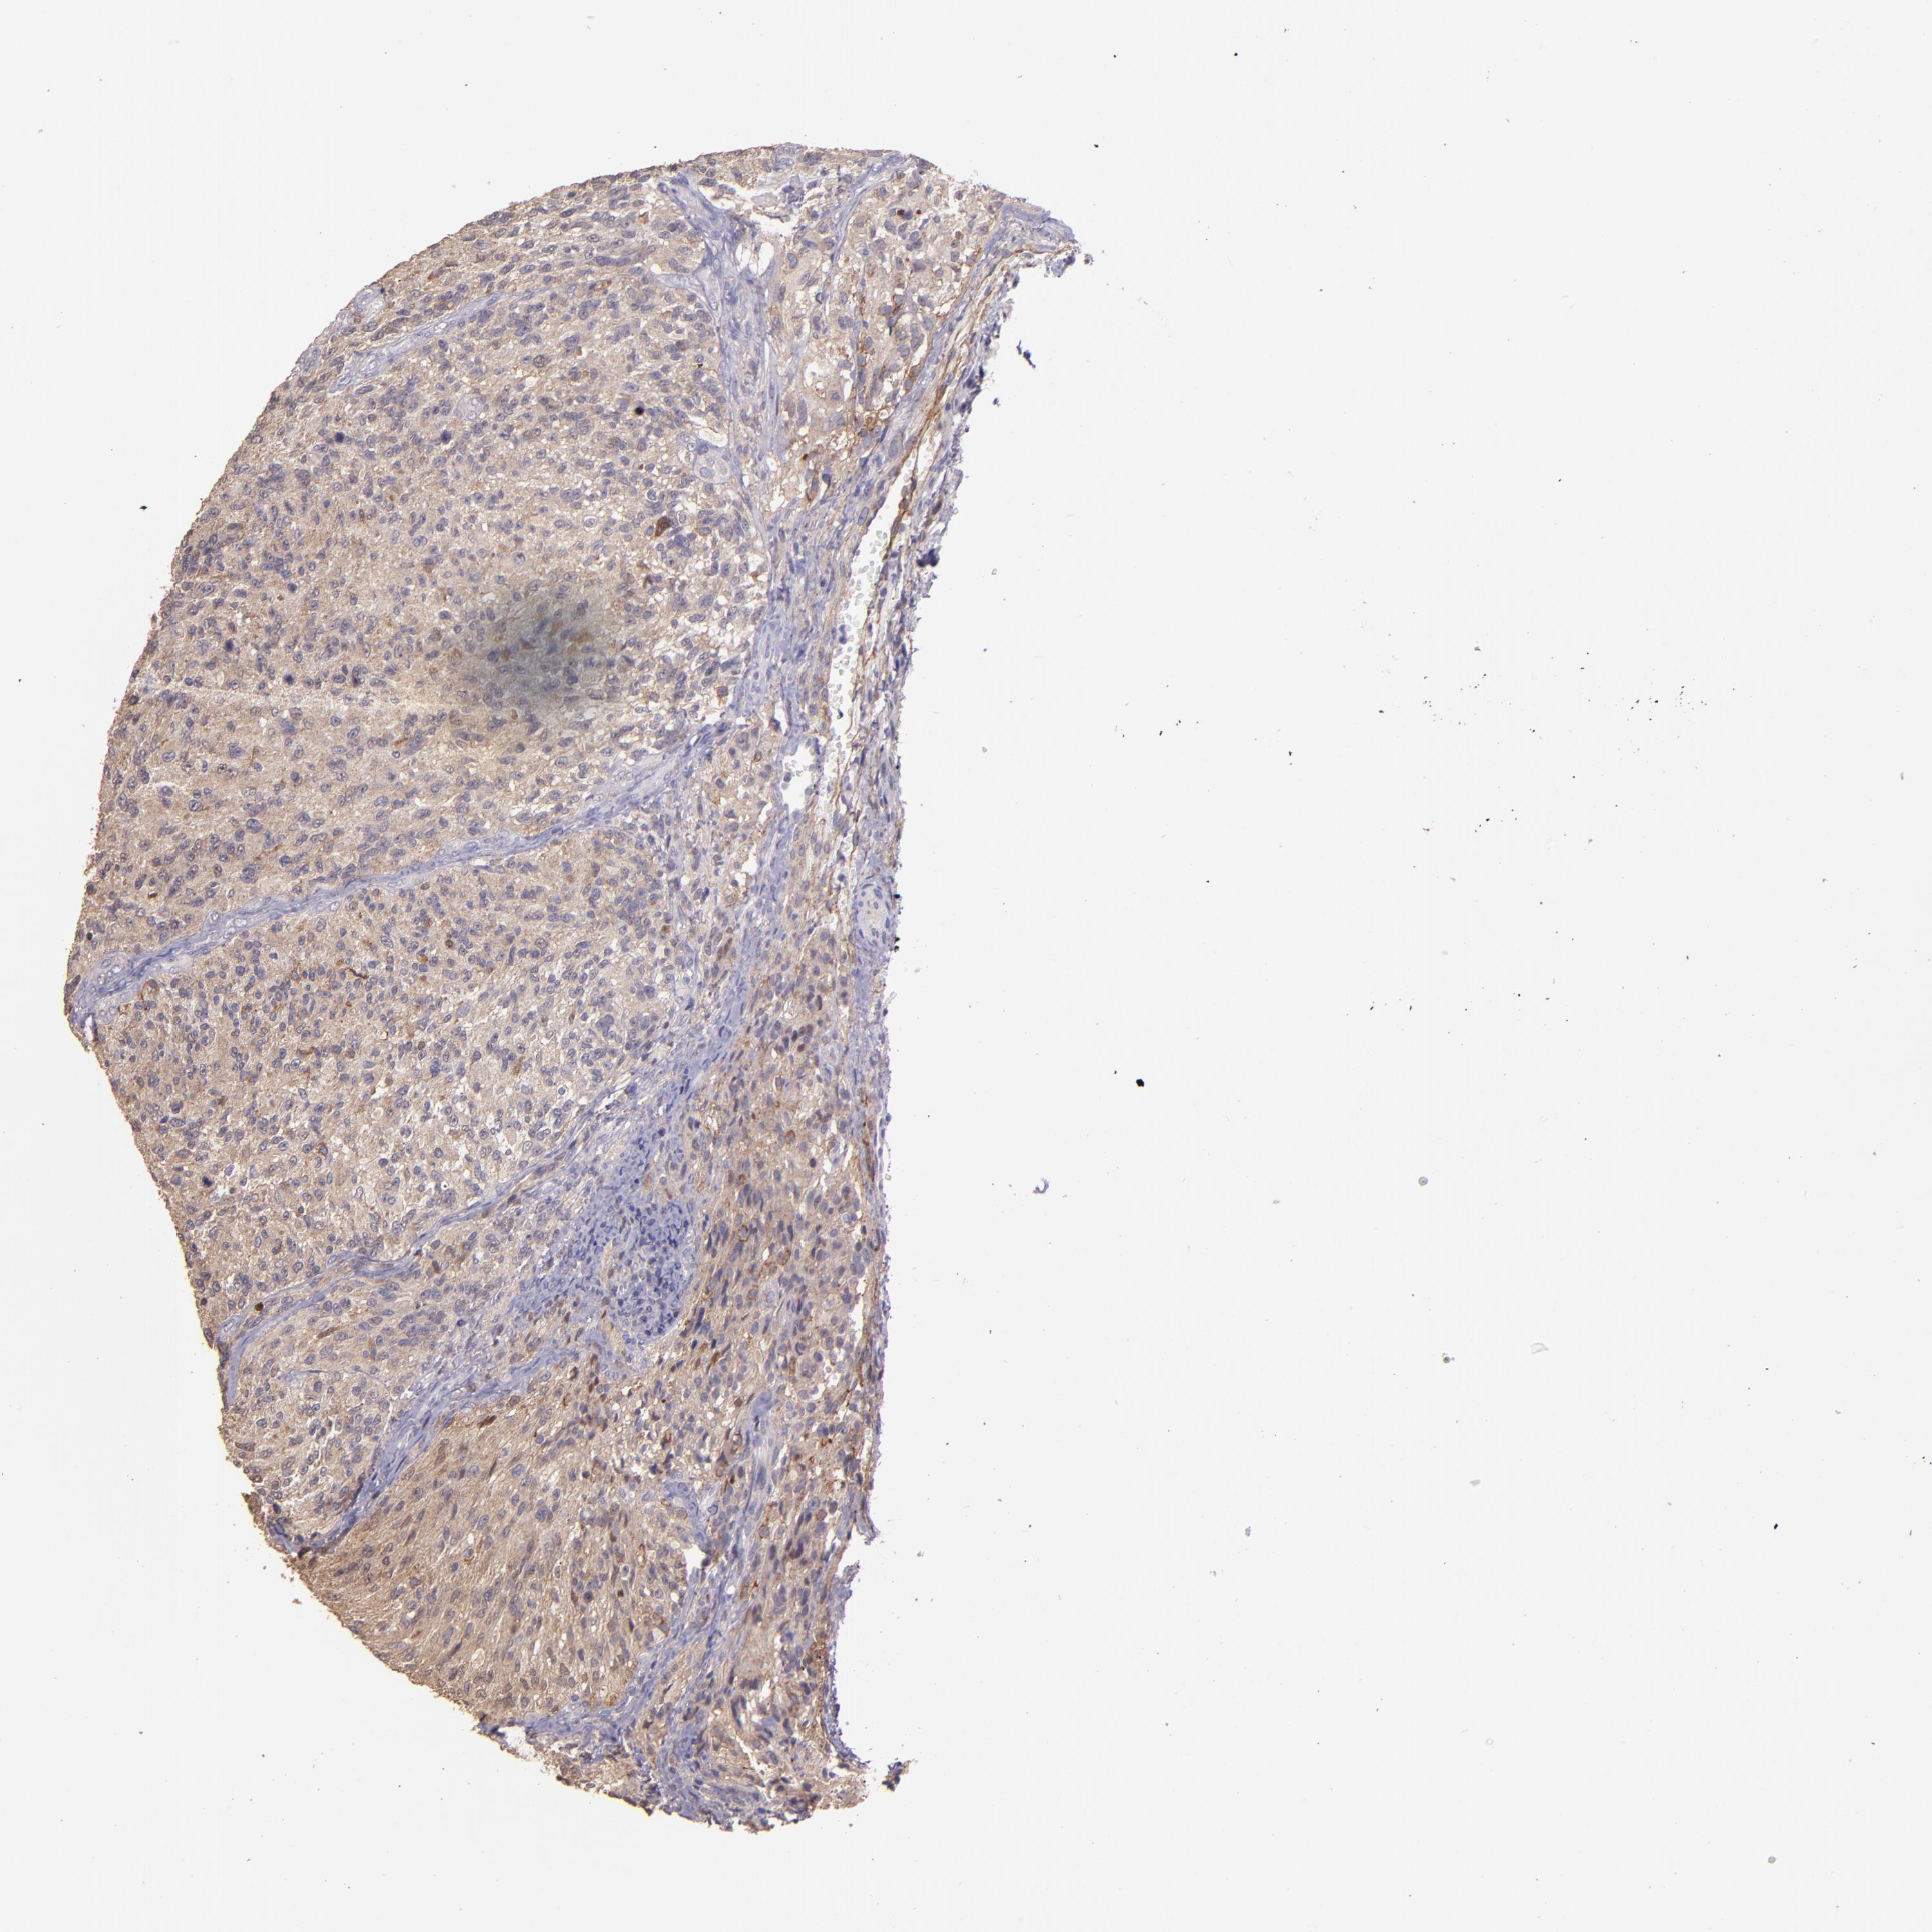

GLIOMA - Protein expressioni

A mouse-over function shows sample information and annotation data. Click on an image to view it in a full screen mode. Samples can be filtered based on level of antibody staining by selecting one or several of the following categories: high, medium, low and not detected. The assay and annotation is described here.

Note that samples used for immunohistochemistry by the Human Protein Atlas do not correspond to samples in the TCGA dataset.

Antibody stainingi

Antibody staining in the annotated cell types in the current human tissue is reported as not detected, low, medium, or high, based on conventional immunohistochemistry profiling in selected tissues. This score is based on the combination of the staining intensity and fraction of stained cells.

Each image is clickable and will lead to virtual microscopy that enables deeper exploration of all samples and also displays staining intensity scores, fraction scores and subcellular localization as well as patient and tissue information for each sample.

Antibody HPA001667

Antibody CAB016724

Staining

High

Medium

Low

Not detected

Intensity

Strong

Moderate

Weak

Negative

Quantity

>75%

75%-25%

<25%

None

Location

Nuclear

Cytoplasmic/membranous

Cytoplasmic/membranous,nuclear

Glioma, malignant, High grade

Glioma, malignant, Low grade

Glioma, malignant, NOS